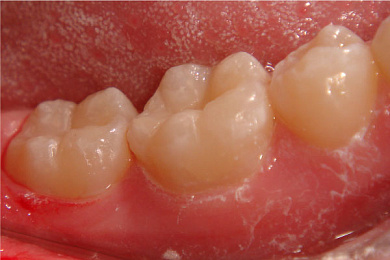

Если же обратиться с ребенком к стоматологу на ранней стадии развития, то возможно лечение с применением технологии ICON, которая состоит в нанесении на поврежденный участок специального композитного материала без предварительного бурения.

Детские стоматологи клиники «Интердентос» знают, как подобрать правильный ключик к каждому пациенту. После необходимых процедур, ребёнок может самостоятельно выбрать цвет пломбы, и посещение стоматолога превратится в интересную игру! Но это лишь малая доля преимущество нашей клиники. Главное – мы гарантируем, что сделаем всё возможное, чтобы зубы ваших детей были красивыми и здоровыми!